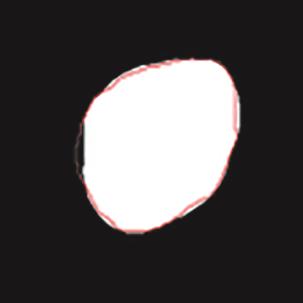

乳腺癌是全球女性最常见的恶性肿瘤之一,准确的病变分割对于乳腺癌的早期诊断与治疗具有重要意义。然而,由于病变形态的多样性以及超声成像机制的复杂性,现有基于深度学习的乳腺超声图像病变分割方法在分割准确性方面仍面临巨大挑战。为进一步提升乳腺超声图像中病变区域的分割精度,该文基于经典U-Net架构,提出了一种新型乳腺超声图像病变分割网络(CWSASKM-BBAM-Net)。首先,在网络中引入逐通道空间自适应选择核卷积模块(CWSASKM),根据不同通道的语义特征为每个空间位置自适应选择感受野大小,以增强多尺度信息的建模能力;然后,引入双向边界感知机制(BBAM),通过融合正向与反向注意力,对目标显著区域及其边界进行协同建模,同时逐步提升对非显著区域与病变区域的区分能力,以进一步强化边界信息的表达;最后,在3组公开乳腺超声图像数据集(BUSI、UDIAT和STU)上开展分割实验。结果表明:该方法在数据集BUSI上的杰卡德指数、精确率、召回率和Dice相似系数分别为71.97%、82.85%、81.40%和80.44%,较次优方法分别提升1.69、1.05、1.28和1.84个百分点;在数据集UDIAT上,这4项指标分别达到78.14%、88.31%、86.73%和86.10%,较次优方法分别提升了2.75、2.04、0.56和2.01个百分点;在外部数据集STU上,该方法也取得了优于其他方法的整体表现。实验结果表明,CWSASKM-BBAM-Net在乳腺超声图像分割任务中展现出更优的整体性能。